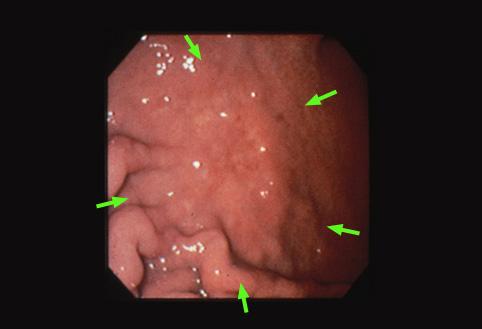

질환(병리주체)의 분류 악성 상피성종양/인환세포암

부위(장기별) 위(부위)/체부

검사방법 내시경

종양의 육안분류 0형(표재형)/IIc형(IIc)

종양의 최대경(밀리미터) 35~40

종양의 심달도 m